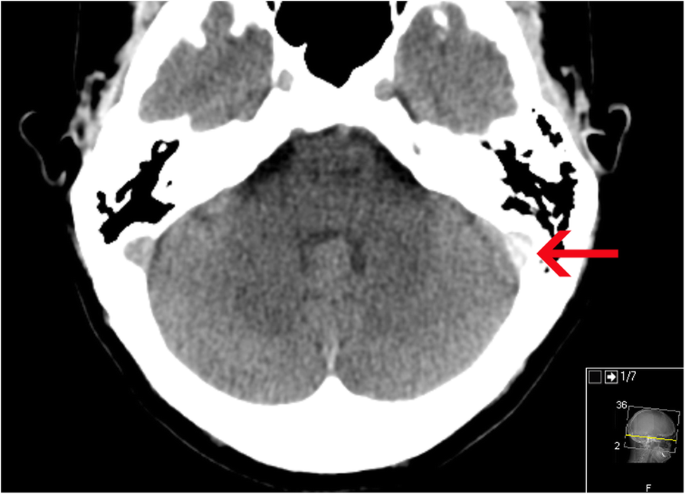

a Region of interest delineation in the superior sagittal sinus was performed on 0.63 mm thin axial slices at the level above the lateral ventricles as a triangular shape in the sinus. b Region of interest delineation in the left and right sigmoid sinus was performed on axial 0.63 mm thick slices at the level of the internal acoustic meatus in the sinus. Red arrow indicates region of measurement. c A region of interest (ROI) in the left and right transverse sinus was performed on reformatted 5 mm sagittal slices at the level just lateral to the lateral ventricles as a triangular shaped ROI. Red arrow indicates region of measurement. d A region of interest (ROI) in the torcular herophili was delineated on sagittal reformatted 0.63 mm thick slices

In blinded reevaluation, one patient (1/104, 1.0%) had suspicion of CVST presenting as an intradural high density (Fig. 2) with the highest HU in the left sigmoid sinus (HU = 89), while 103 patients (99.0%) had no suspicion of CVST on neCT.

Data on HU in unaffected sinuses in the 103 CVST-negative patients is presented in Table 1. Median HU in the torcular herophili was 52.0 (IQR 48.0–55.0), superior sagittal sinus 57 (IQR 54–60), 59 in left (IQR 55–64) and right (IQR 54–63) sigmoid sinuses and 57 (IQR 54–60) and 56 (IQR 54–59) in left and right transverse sinus. The maximum HU in the patient with suspected thrombus on neCT was 89 in the thrombus measured in the left sigmoid sinus (CVST confirmed by CTV as depicted in Fig. 3). An inverse correlation between HU and patient age was found, with HU decreasing with increasing age (r = − 0.20, p = 0.04). The variance of HU was highest in the sigmoid sinus (6.1–6.6 HU) and lowest in transverse sinuses and torcular herophili (4.1–4.5 HU).